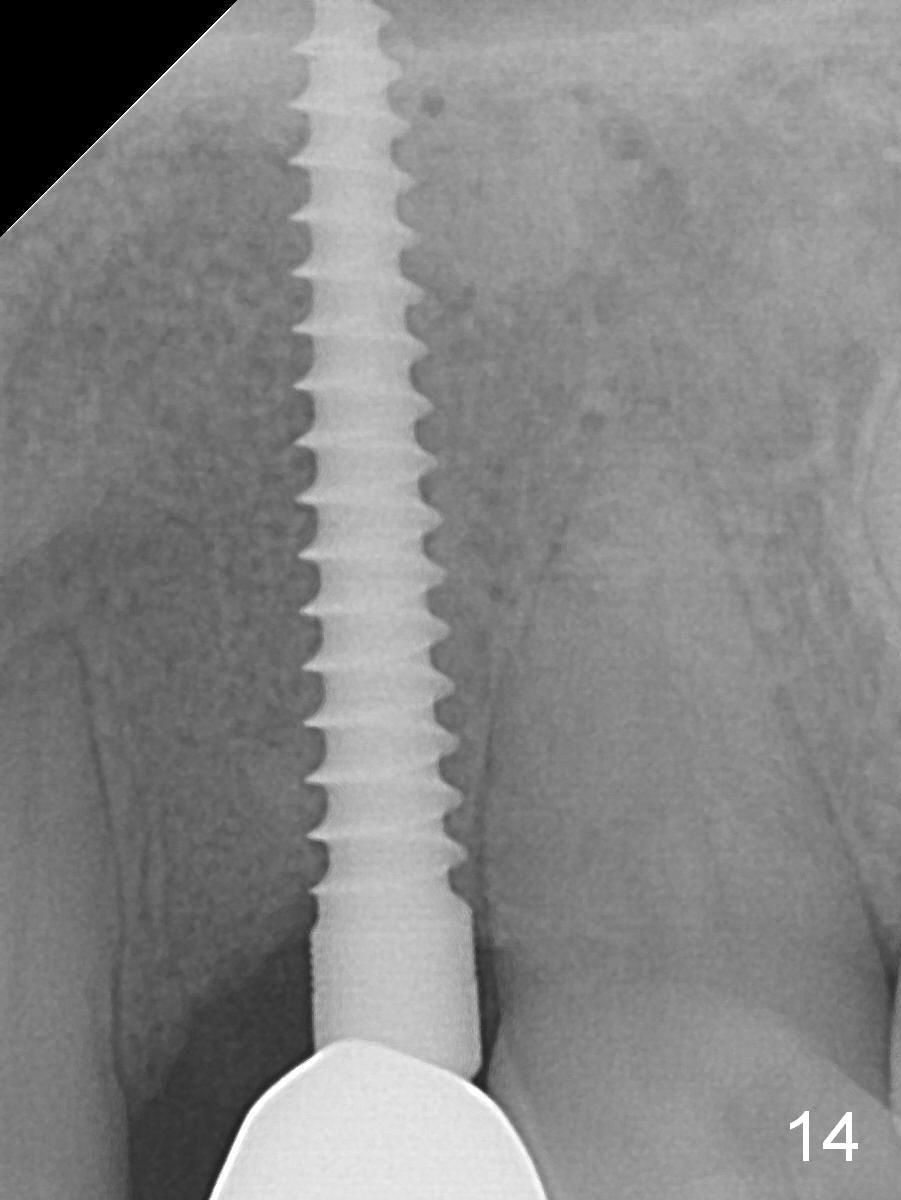

There is no gingival recesssion (data not shown) or bone loss around the implant 1 year post cementation (1 year 9 months postop; Fig.14).